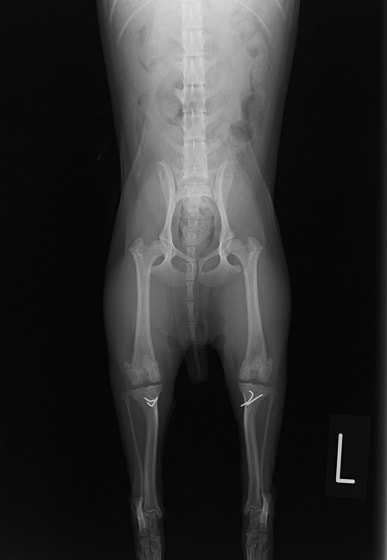

■ 症例24 キャバリア 7か月

左右膝蓋骨内方脱臼(左:グレードⅣ 右:グレードⅢ)

以前から左右後肢の跛行が認められ、整形外科学的検査・レントゲン検査により左右の膝蓋骨脱臼が認められた。症状が重度である左膝の膝蓋骨脱臼整復術を行った。外科手技は縫工筋及び内側広筋の解放、脛骨粗面の外側転位、滑車ブロック形造溝術、内外側関節方の縫縮を実施した。術後一か月時点で、左の膝蓋骨は安定しており経過は良好である。

本症例は成長期における重度の膝蓋骨脱臼であり、術後の再発の可能性もあるため、経過をしっかりと観察していく必要がある。また、今回手術を実施していない右膝に関しても経過を観察し、手術を検討していくこととする。